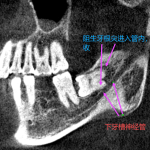

- MRI:T2WI显示肩胛骨深面新月形高信号(滑囊积液),滑囊壁>2mm为异常

- 3D-CT:测量Luschka结节大小,>3mm为病理性

- 超声:无法直接显示滑囊,但可识别骨皮质表面低回声炎性渗出间隙及肋间血管

注意:很多患者影像学为阴性,可以进行诊断性肩胛骨下局麻药注射。